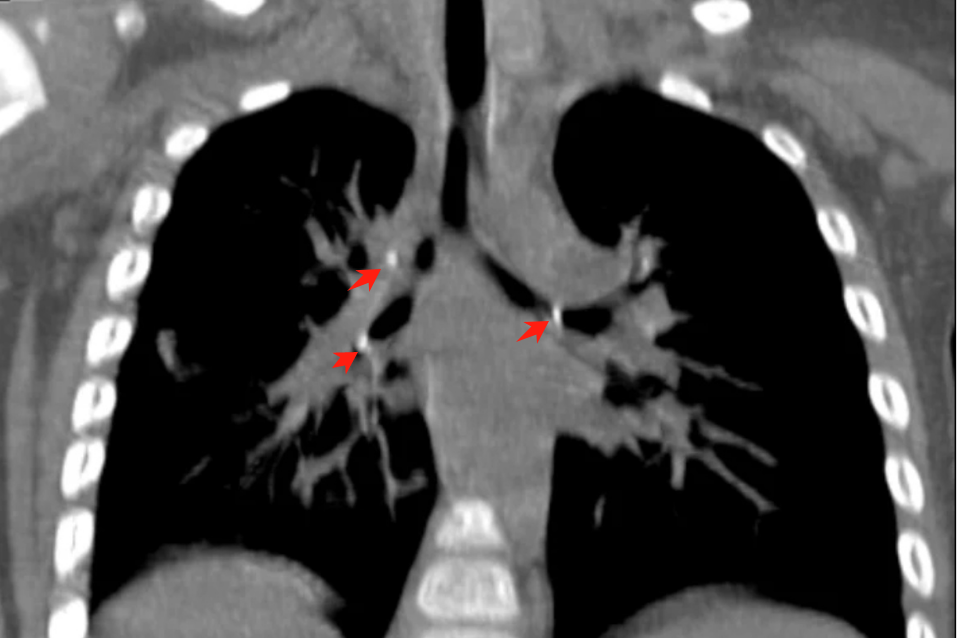

辗转多家医院后小奉夫妇慕名来到了郴州市儿童医院,给患儿完善了肺部三维CT检查,不做不知道,一做吓一跳,原来患儿右肺上叶、下叶基底段左主支气管存在多发异物。

患儿1月前因咯血到儿童感染科住院治疗,完善相关检查后最终诊断为:1. 肺结核;2. 左肺舌叶狭窄。

出院后给予规律抗结核治疗,因气道存在狭窄,再次到儿童感染科住院进一步治疗,请袁树贞医师协助治疗,经研讨分析后,拟行支气管镜下支气管球囊扩张联合冷冻消融术。

完善术前准备后,手术有条不紊地进行,袁医生操作:进镜、定位、选择合适球囊、枪泵增压、球囊扩张(充气-扩张-抽气)、冷冻消融、再次进镜检查......经过一系列操作,原镜下可见狭窄,堵塞约80%面积的支气管管腔终于通畅。